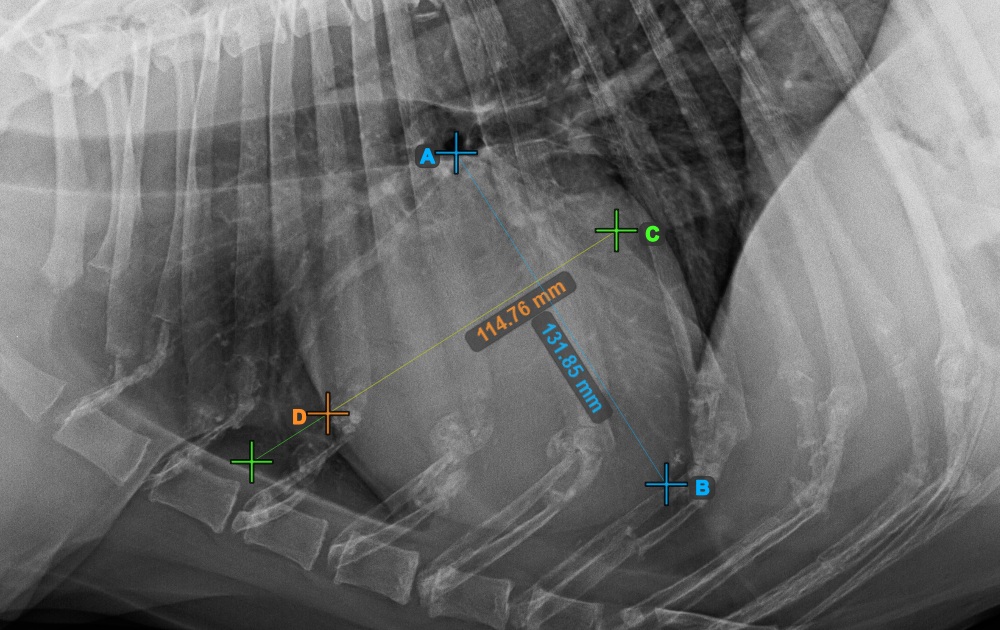

Complete the short axis of the heart by marking the widest left (caudal) point.

The image below represents the typical placement of the most caudal point on the short axis of the heart.